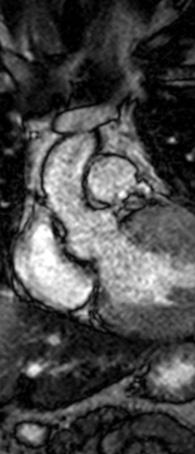

Figure 1: Vista coronal de resonancia magnética cardíaca IVS engrosamiento 3,0cm e infiltración fibrosa septal.

INTRODUCCIÓN

• La resonancia magnética cardíaca

Cardiovascular Disease Fellowship Program, St. Figure 2: Vista sagital de la resonancia magnética cardíaca IVS engrosamiento de 3,0 cm e infiltración fibrosa septal.

posterior mostró un engrosamiento del tabique interventricular de 3,0 cm, así como una infiltración fibrosa del tabique confirmando el diagnóstico de MCH.

Figure 3: Vista axial de resonancia magnética cardíaca IVS engrosamiento 3.0cm e infiltración fibrosa septal.